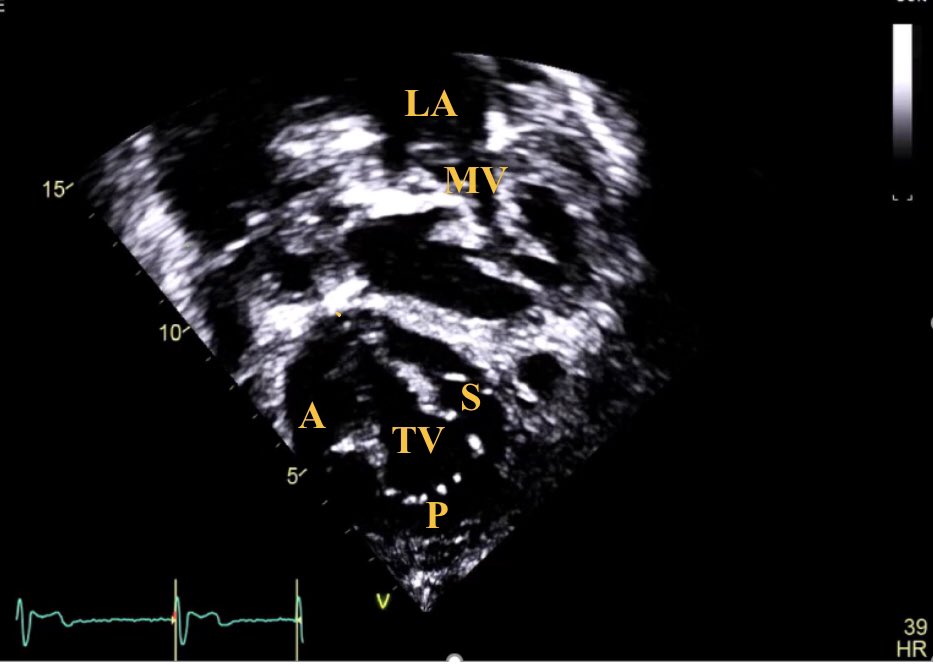

4/6 Same patient, subcostal images can provide an excellent visualization of the tricuspid leaflets morphology (clip attached below)... #echofirst

5/6 Subcostal view showing the tricuspid valve morphology #echofirst